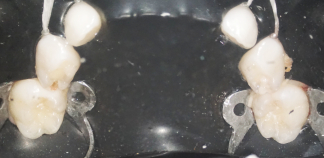

До лечения

Жалоба на сильно разрушенный жевательный зуб.

Как лечили

После нескольких прелечиваний откололась стенка зуба. Зуб восстановлен коронкой из высокопрочной пластмассы.